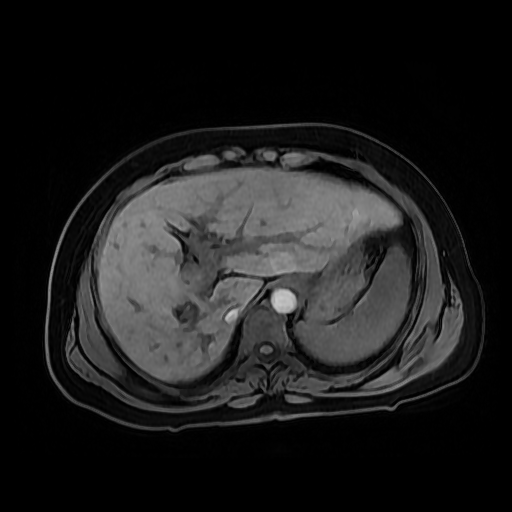

HISTORIA DEL PACIENTE

Paciente de sexo femenino, de 56 años de edad, refiere dolor en cuadrante superior derecho, indica que le realizaron colecistectomía de hace mas o menos 7 años, presenta cuadro de ictericia de 6 meses de evolución. Médico tratante le solicita estudio de Resonancia de vías biliares (Coilangioresonancia)

Se prepara a paciente previo a ingreso a zona 4 del área de resonancia magnética, paciente se presenta con catéter en región anterior del antebrazo, se utiliza bobina de abdomen de 16 canales y se procede a obtener localizadores en los tres planos, para luego adquirir imágenes en diferentes planos, en secuencias espin echo, eco de gradiente, secuencia de difusión. Se utiliza medio de contraste hepatoespecifico con dosis sugerida por fabricante.

HALLAZGOS IMAGENOLOGICOS

Se observa dilatación de las vías intra hepáticas a expensas de sus ramas hepáticas derecha, anterior y posterior, hepática izquierda y hepática común. El hepático común da la apariencia de estar anastomosado a un asa de intestino, lo que sugiere la posibilidad de una cirugía entero biliar.

No se logra observar el colédoco.

1. Dilatación de vías biliares intrahepáticas

2. Anastomosis entero biliar

3. Colangitis aguda